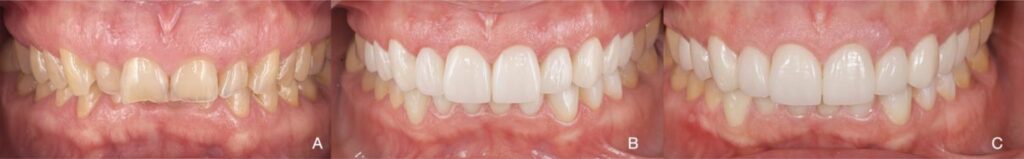

Figure 3. Patient 3. Generalized severe pathological tooth wear (TWES 2.0). (A) Intraoral situation:

deep bite and occlusal relationships shown by a patient with severely worn anterior teeth. (B) Occlusion

after orthodontic and restorative treatment, indicating aesthetic and functional improvement.

Felspathic vestibular veneers from 1.5 to 2.5, CAD-CAM nanoceramic palatal veneers from 1.3 to 2.3,

lithium disilicate veneers from 3.3 to 4.3 and a direct stamped composite resin in the posteroinferior

sectors (3.4–3.6 and 4.4–4.6). (C) A 5-year follow-up photograph. Note the maintenance of occlusal

contact relationships. (D) Initial orthopantomography. (E) Final orthopantomography showing the

supplementation of all teeth with an endodontic treatment in 1.4 due to previous necrosis.